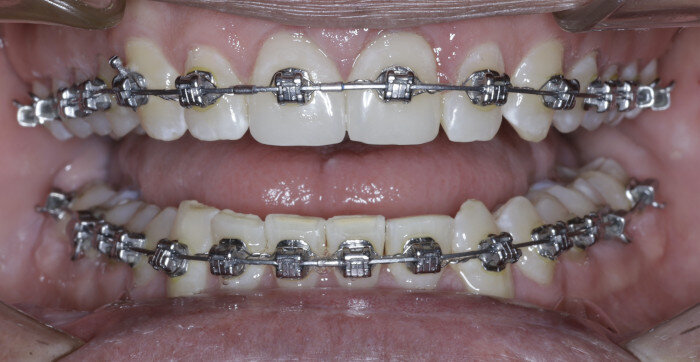

The anterior gummy smile The anterior gummy smile is one in which the patient shows excess gingival display from maxillary canine to maxillary canine (Figs. 4 & 5, beginning of treatment). This takes into account the ideal crown shape and size, where the patient has true anterior maxillary excess and is not just in need of a gingivectomy or crown lengthening procedure. To best determine if gummy smile treatment is needed in the anterior, the authentic smile photograph is used, alongside measurement of the incisor display at rest. If the resting incisor display is greater than threequarters in the adult patient without altered passive eruption, gummy smile treatment is needed. These cases are treated using two TADs placed between tooth #13 and #12 or between #22 and #23 using a 1.6 × 6.0 mm TAD. If slight posterior impaction is desired, bite turbos with Triad Gel (Dentsply Sirona) are placed on teeth #37 and #47 and squeezing exercises used to impact posterior molars engaging the posterior fibres of the temporal muscles (60 squeezes six times per day).

TADs are placed at the second visit with a 14 × 25 mm copper (Cu) and nickel–titanium (NiTi) wire and are tied from the anchor to the wire with an elastic thread (surgical thread; Fig. 6). Once the patient has progressed to larger Cu–NiTi wires and stainless steel, the TADs are tied to the wire using a power chain looped to the wire, or NiTi closing springs, depending on the thickness of the tissue (Figs. 7 & 8).

Once the intrusion has been completed, the TADs are tied to the wire and vertical elastics are used to close the bite without relapse of the intrusion. If buccal crown tip is seen, owing to the movement created by the intrusion, a power chain torquing sling is used to encourage lingual crown tipping and to prevent flaring of the incisors (Fig. 9). Once the case has been completed, the appliance is removed and a gingivectomy is performed to idealise the tissue shape and the final contours are made to the hard tissue (Figs. 10–12, end of treatment).